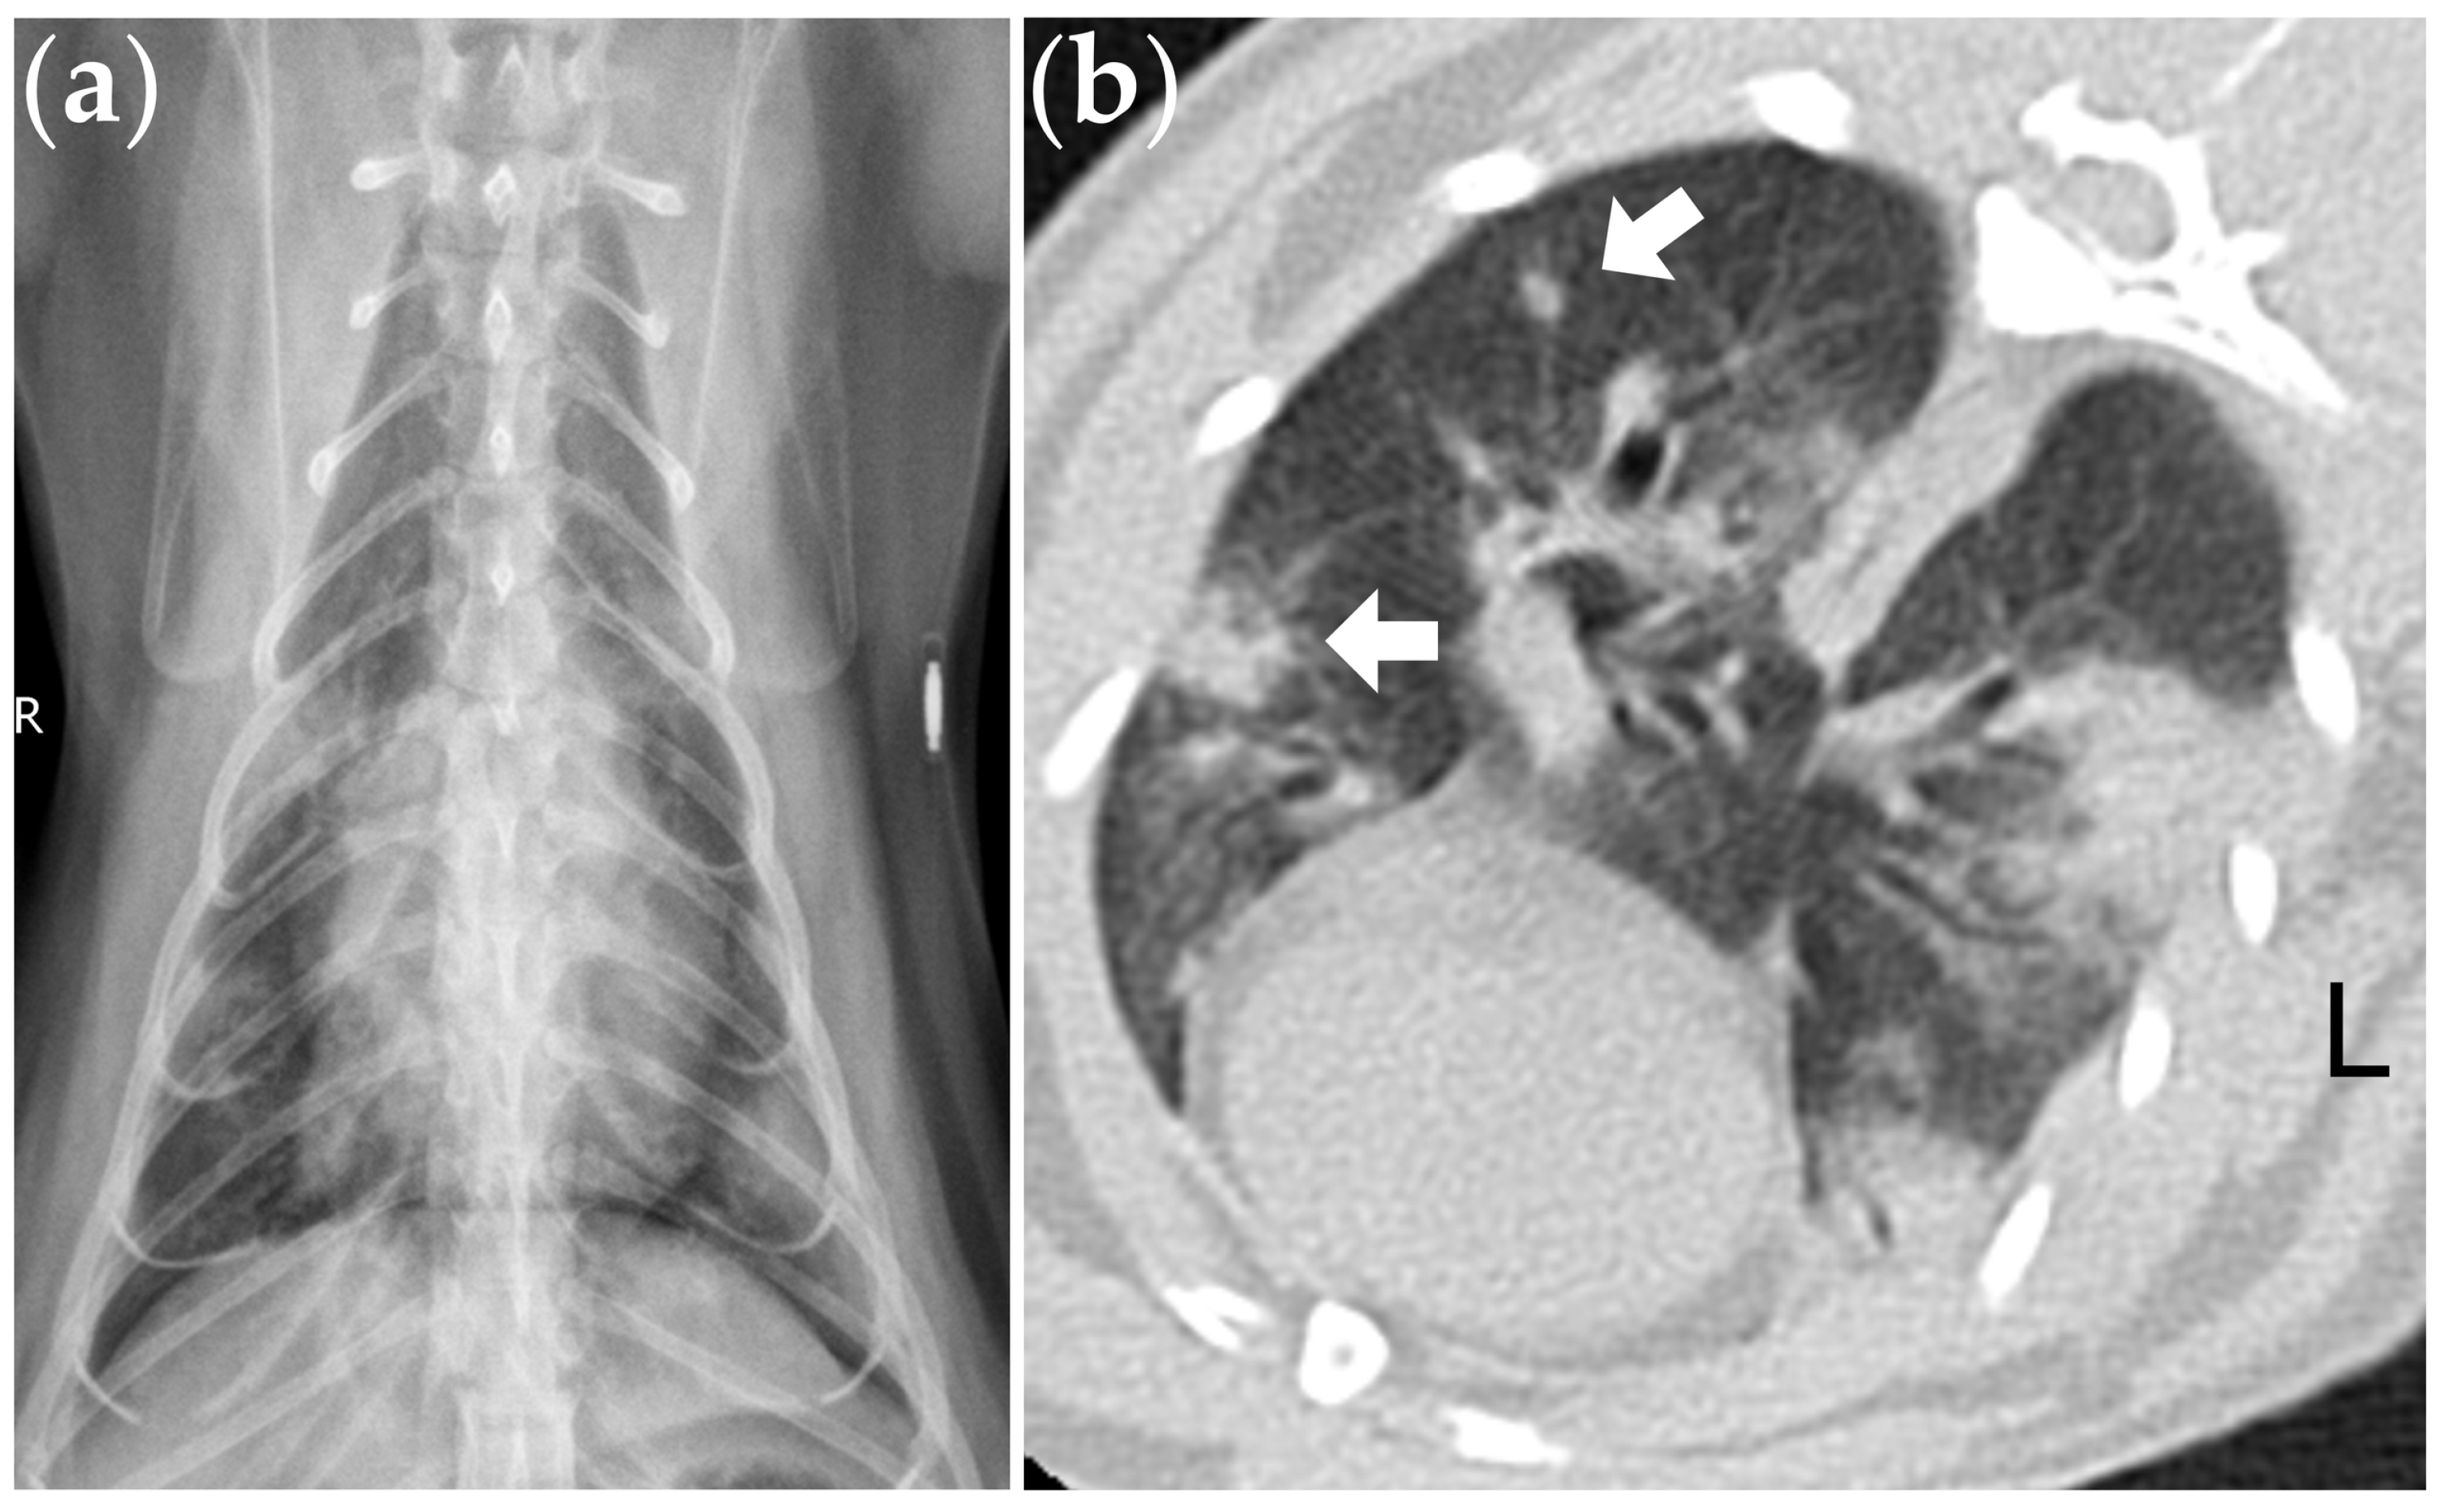

The FeCoV RT-nPCR testing of the BAL samples from these 24 cats revealed a 13% (3/24) positivity rate, with no other bacterial, fungal, or viral pathogens identified in these three cases. Of the three cats with positive RT-nPCR results for FeCoV, two cats also had a positive IFA result, confirming the presence of FeCoV within the cytoplasm of alveolar macrophages in the BAL fluid (Figure 1). These three cats were diagnosed with suspected FeCoV-associated lung disease. All three cats presented with multinucleated cells based on BAL cytology (Figure 1), and two cats presented with nodular lesions on the thoracic CT images (Figure 2).

Figure 2. (a) Thoracic radiography from a cat with positive RT-nPCR result for FeCoV in the BAL fluid, showing multifocal distribution of abnormal opacities involving more than one lung lobe. (b) Lung high-resolution CT of the same cat revealed multifocal consolidation lesions and nodular lesions (arrow). The CT scanning was performed under sedation without general anesthesia (window width: 1500 HU; window level: −400 HU).